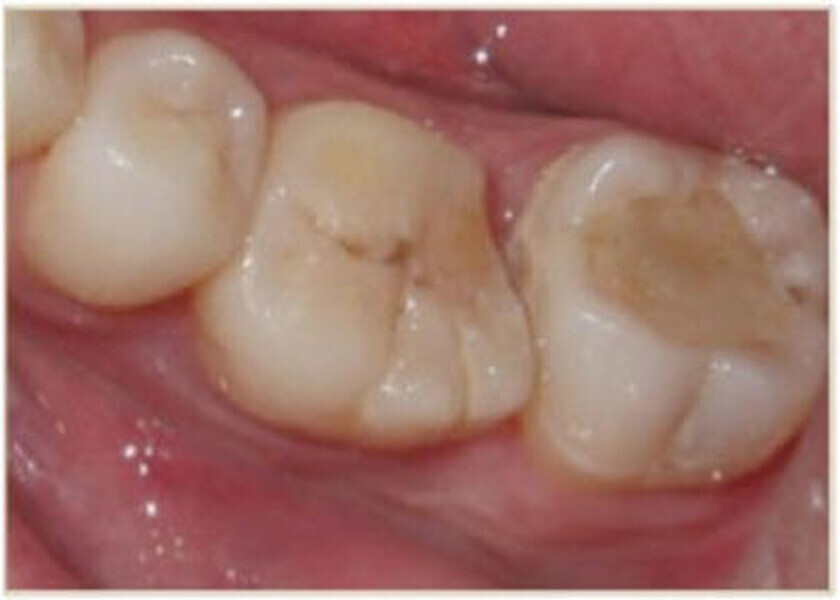

Leczenie endodontyczne autogennego przeszczepu zęba